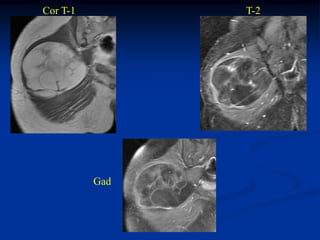

Case #1204.1

31 year female with soft swelling in leg for many years

Axial CT

Cor Ct

Cor T-2   Sag Gad   Sag Gad

Axial Gad   Axial Gad